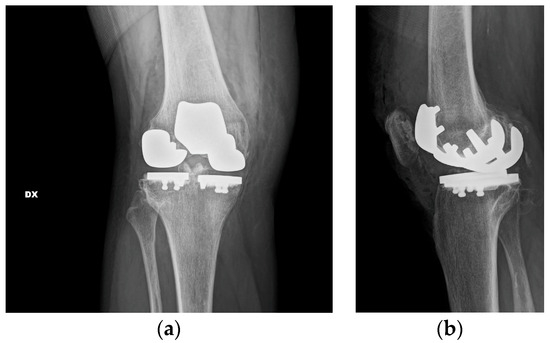

One-Stage Tricompartmental Hypoallergenic UKA for Tricompartmental Osteoarthritis: A Case Report

2. Case Description